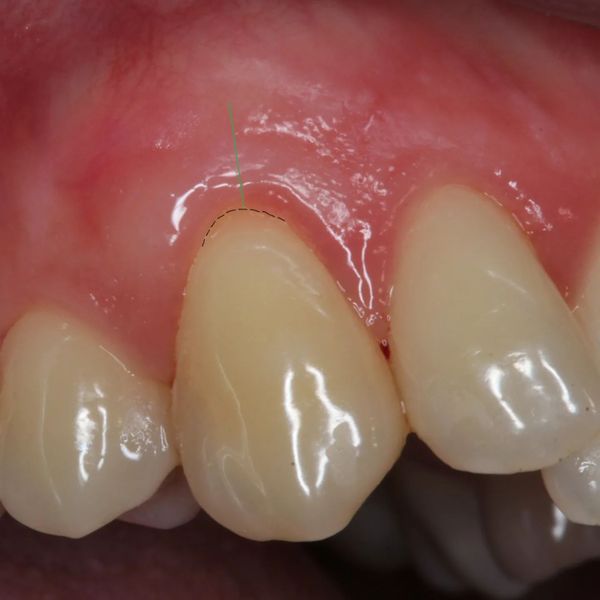

Prekrivanje recesija gingive spada u visoko specijalizirane mikrokirurške zahvate u parodontologiji.Osim samog prekrivanja recesije važna je i kvaliteta gingive oko zuba(pričvrsna gingiva). Predvidljivost rezultata nakon operacije ovisi o tipu i zahvaćenosti recesije.

Ovdje je prikaz slučaja operativnog zahvata recesije(Miller klasa 1) i situacija 2. godine nakon zahvata.